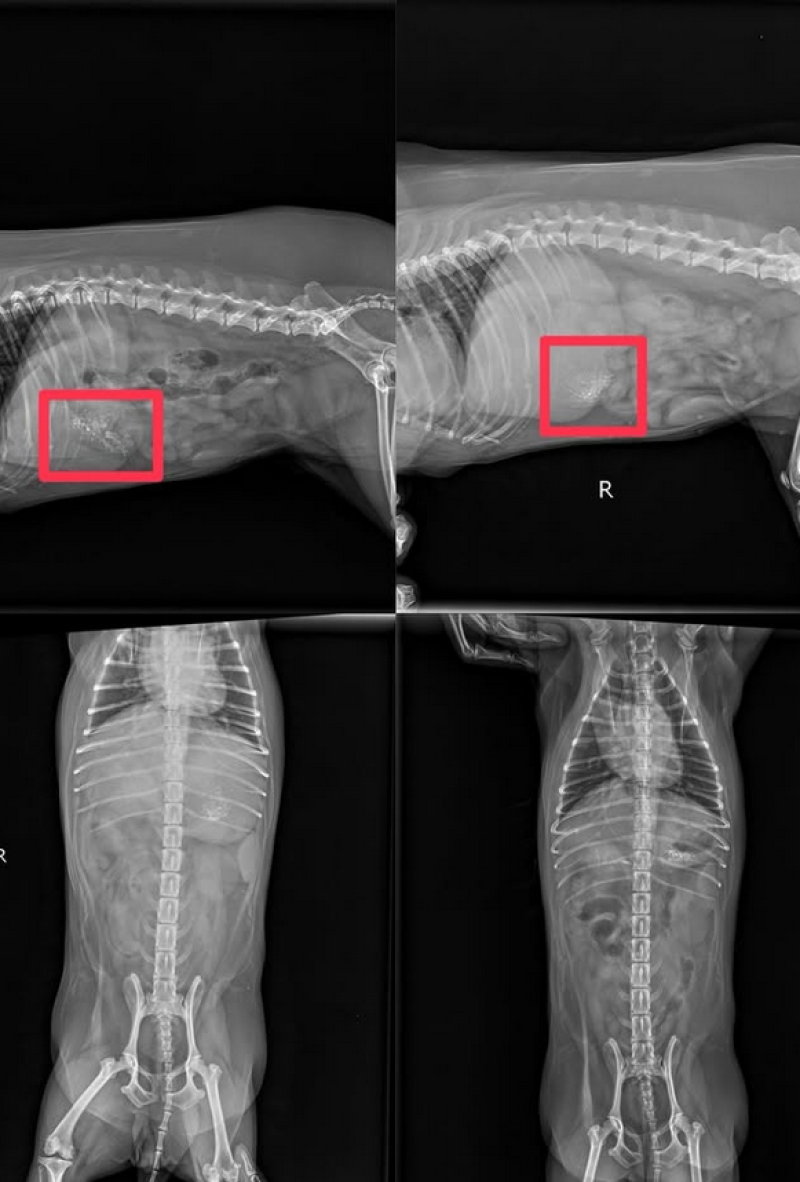

น้องถูกเลี้ยงดูในระบบปิด ที่มีกล้องวงจรปิดที่บันทึกไว้ตลอดเวลา หมีมีอาการปวดท้องและอาเจียนอย่างหนัก ไม่ต่ำกว่า 10 ครั้ง หลังจากพบแพทย์ ได้ X-Ray, ส่องกล่อง และอัลตร้าซาวด์ พบว่ามีเศษที่มีลักษณะแข็งคล้ายกระดูกและไม้ กระจายอยู่เต็มกระเพาะอาหาร ลักษณะมีทั้งสีขาวแหลมเป็นก้อนแข็ง คล้ายกระดูก ปูน,สีดำและสีน้ำตาลคล้ายเศษไม้ คุณหมอได้ทำการล้างท้อง แต่เศษดังกล่าว ยังคงติดค้างอยู่ในบริเวณท้องตอนนี้แพทย์กำลังดำเนินการรักษาอย่างต่อเนื่อง